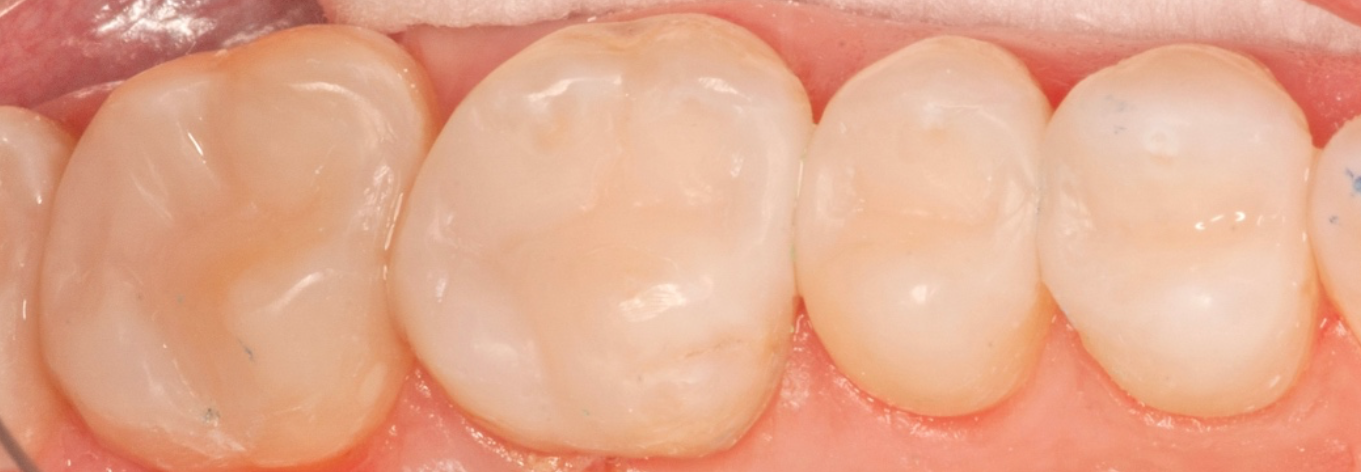

The below is of a woman in her mid-30’s who came to us as a new patient, wanting to be proactive and address early signs of oral disease before becoming serious issues. During the New Patient Experience, we showed her photographs and xrays of her upper right posterior teeth, with old failing “fillings”, and she was concerned.

After much discussion, and showing her photographs of prior cases utilizing the minimally-invasive technique, she chose the Maximized Adhesive Dentistry (MAD) protocol. After administering local anesthetic, we excavated all the old failing fillings and resulting tooth decay, preserving all the healthy enamel that remained.

We then removed all debris and contaminants, thoroughly disinfected the teeth, and incrementally built back and sculpted with composite… no crowns, no root canals. Truly a great example of where art and science meet in the practice of dentistry! This quadrant of the mouth was restored in one long morning appointment.